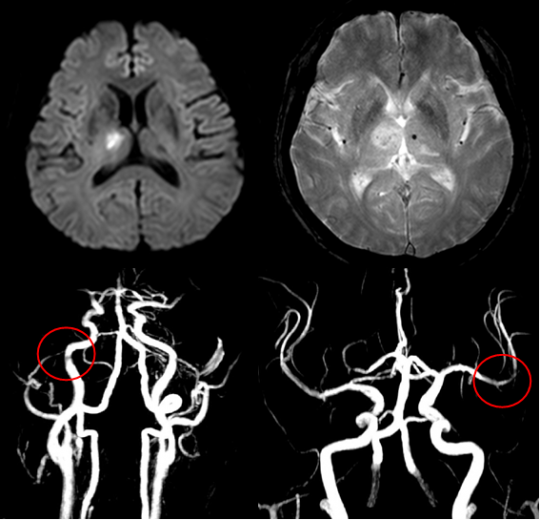

먼저, 뇌경색이 무엇인지에 대해 간단히 설명드리겠습니다. 뇌경색은 뇌에 공급되는 혈액이 차단되어 뇌세포가 손상되는 상태를 의미합니다. 대개 두 가지 종류가 있으며, 하나는 혈전으로 인한 허혈 뇌경색이고, 다른 하나는 출혈로 인한 뇌출혈입니다. 이 두 가지 모두 뇌에 큰 영향을 미치며, 생명을 위협할 수 있는 심각한 질환입니다.